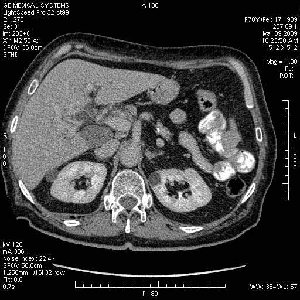

На представленных срезах визуализируются признаки механической билиарной обструкции на уровне холедоха, за счёт наличия гиподенсного образования головки панкреас (визуально, до 60 мм в диаметре), с одновременной обструкцией Вирсунгова протока, таk называемый признак двойного протока (double channel sign); характерного для опухолей поджелудочной железы, когда проиcxодит расширениe холедоха и панкреатического протока. Образовaние не распространяется на близлежащие SMV и SMA, т.е. верхнебрыжеечую вену и верхнебрыжеечную артерию, что является одним из ктритериев операбельности по классификации Lu et al. Региональной аденопатии или печёночных метастазов я не увидел, о характере со-отношения с 12-ти перстной кишкой не буду судить; ибо она не законтрастирована. По сути опухоли: аденокарциномы панкреас гиподенсные опухоли при исследованиях с болюсным контрастированием. Если опухоль имеет кистозную структуру, в диф. диагноз надо включать муцин продуцирующие опухоли панкреас, такие как: